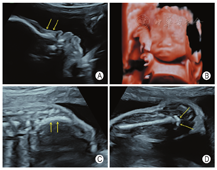

孕妇,21岁,孕4产0,孕27周。因外院羊水染色体核型分析提示47,XXX来我院行胎儿系统超声筛查。超声检查显示:胎儿生物学测量相当于孕23周+,胎儿面中部凹陷,鼻部短小,鼻梁低平,尾椎多个椎体融合、回声增强,左侧肱骨两端干骺端及双侧股骨近端干骺端可测及数个点状强回声斑(图1);双手掌及双足板短小,以指(趾)端明显,双手掌及双足板多个骨性结构短小、部分骨性结构未能显示(图2);胎儿阴蒂肥大(图3)。超声诊断:①宫内妊娠,中孕单活胎,相当于孕23周+;②胎儿面中部畸形、尾椎畸形、双侧股骨近端及肱骨两端点状强回声斑、双手及双足发育不良——Binder综合征可能;③胎儿外生殖器异常——阴蒂肥大;④胎儿宫内生长迟缓(intrauterine growth restriction,IUGR)。孕妇无华法林服用史等特殊病史,无酗酒史,维生素K依赖性凝血因子、凝血酶原时间正常。

Binder综合征又称上颌-鼻发育不良,是一种罕见的面中部先天性发育异常性疾病,面中部异常主要表现为鼻部短小,鼻背低平,鼻尖下垂,新月形鼻孔、眼距增宽、上颌骨发育不良并错颌畸形等[1]。产前超声表现:主要是在胎儿颜面正中矢状切面显示面中部扁平,包括鼻部短小、额部扁平、额鼻角异常增大、上颌骨平坦、下颌前突等;脊柱畸形是Binder综合征除颜面畸形外最常合并的畸形,包括椎体融合、椎体骨化不良等;长骨干骺端点状强回声斑也是Binder综合征常见的超声表现[2]。Binder综合征胎儿的染色体核型及基因检测多数未见异常,并且目前尚无明确致病基因用于Binder综合征的产前诊断[3]。正常胎儿约32周股骨远端出现次级骨化中心,约37周肱骨近端出现次级骨化中心。本病例为孕27周,具有面中部畸形、脊柱畸形、长骨干骺端点状强回声斑等典型胎儿Binder综合征超声表现,长骨干骺端点状强回声斑提示提前出现次级骨化中心、软骨发育不良可能。引产后标本面中部扁平、鼻梁及鼻翼周围平坦等表现与Binder综合征相符,全外显子组测序未见异常,最终确诊为Binder综合征。本例孕妇无华法林服用史、酗酒史等特殊病史,维生素K依赖性凝血因子、凝血酶原时间等未见明显异常,从而排除了该例Binder综合征是由维生素K缺乏引起。胎儿面中部扁平与50多种综合征相关,如点状软骨发育不良(punctate chondrodysplasia,CDP)、唐氏综合征、Apert综合征等,这些综合征中大多数均存在特征性改变,如Apert综合征特征性超声表现还包括尖头畸形、突眼、双侧对称性并指(趾)畸形等[4]。因此,当超声检查发现上述超声表现怀疑Binder综合征时,应与之相鉴别,尤其需要注意与CDP相鉴别。CDP是由染色体异常或基因突变引起的先天性酶代谢异常性疾病,产前超声表现除了与Binder综合征相似的面中部畸形,还包括脊柱侧弯、四肢不对称缩短等,行过氧化物酶等实验室检查及基因检测可与Binder综合征相鉴别[5]。本例患儿全外显子组测序未见异常,故排除CDP。对于染色体核型正常且孤立性面中部畸形的Binder综合征可通过出生后手术矫正,多数预后良好,合并其他系统复杂畸或合并染色体核型异常的的Binder综合征预后较差。